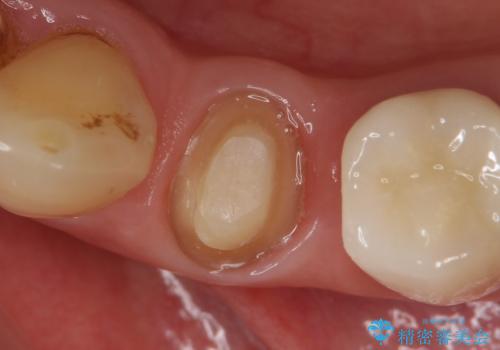

- 左下4番目の歯がなにもしなくてもズキズキ痛むので診て欲しいといらっしゃった方の症例です。

検査の結果、神経の保存は難しかったため、根管治療を行った後オールセラミッククラウンによる補綴を行いました。